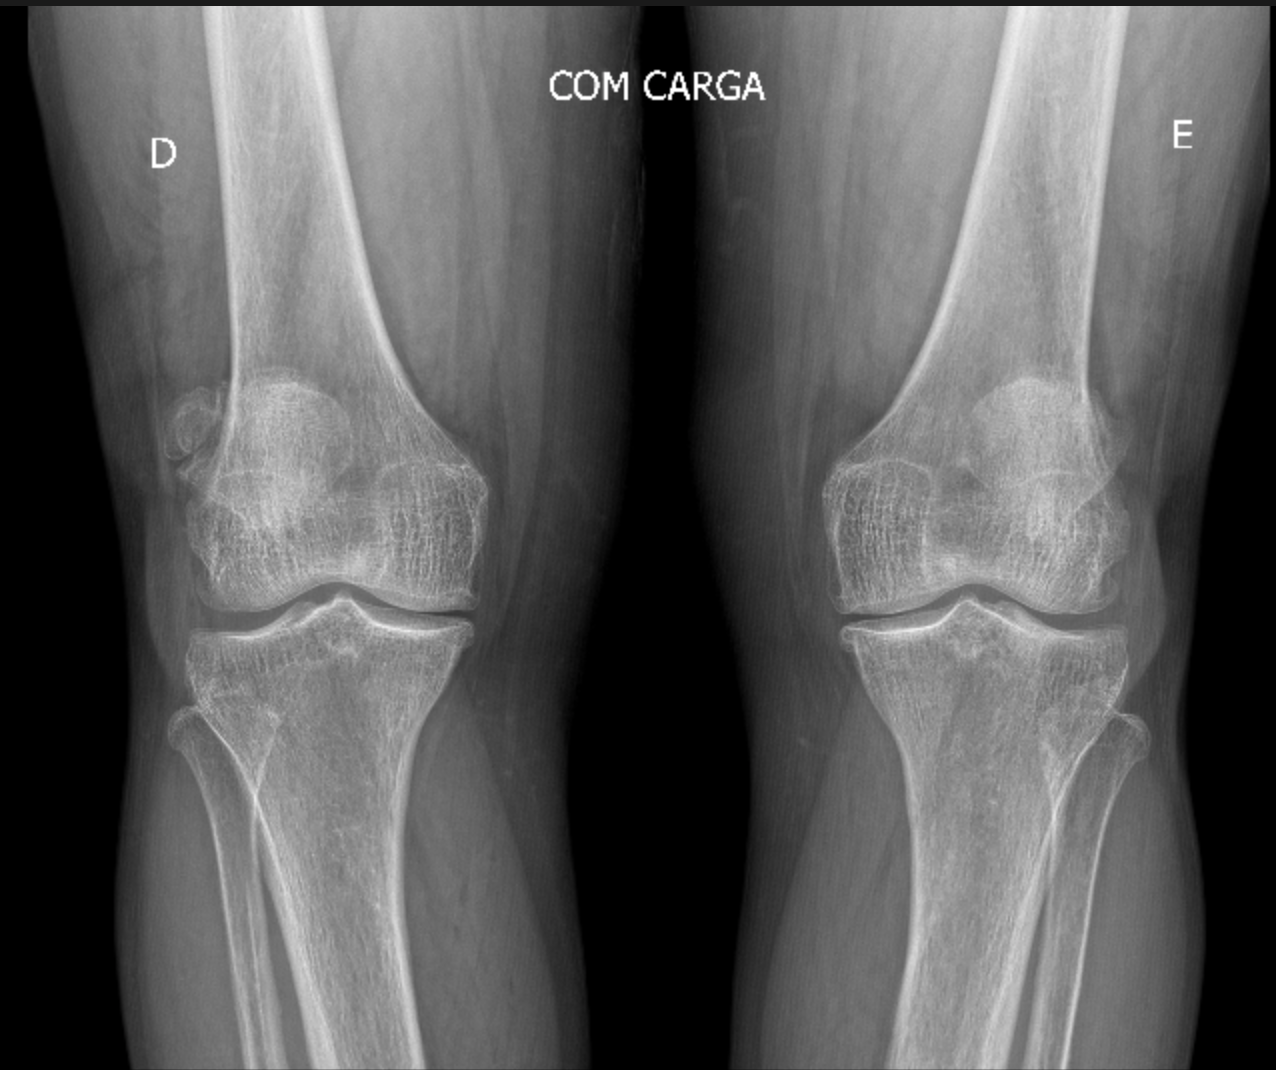

Raio-X de joelho com artrose avançada

Figura 3 - Radiografia em AP com carga demonstrando redução do espaço articular, osteófitos, esclerose subcondral e deformidade em varo (joelhos para fora).

Um diagnóstico preciso é o primeiro passo para um plano de tratamento eficaz. A avaliação é baseada em três pilares:

2. Radiografias (Raio-X): São o exame inicial mais importante. As imagens podem mostrar a diminuição do espaço articular (indicando perda de cartilagem) e a presença de osteófitos, popularmente conhecidos como "bicos de papagaio".